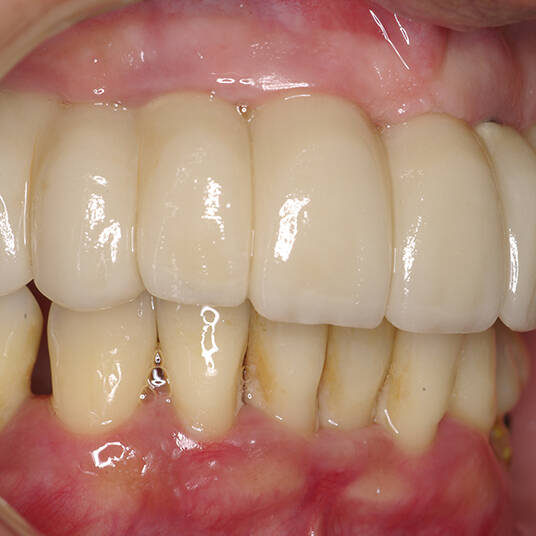

Na Clínica Pontes Odontologia, somos referência em implantes dentários em Fortaleza, oferecendo tratamentos de alta qualidade e tecnologia de ponta. Os implantes dentários são estruturas de titânio posicionadas cirurgicamente no osso maxilar ou mandibular para substituir as raízes dos dentes ausentes. Essa técnica permite a fixação de próteses personalizadas, restaurando a função mastigatória, a estética e a autoestima dos nossos pacientes.

Utilizamos a tecnologia CAD CAM, um sistema avançado que possibilita a confecção precisa das próteses dentárias diretamente sobre os implantes. Esse método inovador garante um ajuste perfeito, um resultado estético superior e proporciona muito mais conforto e durabilidade. Com o CAD CAM, nossos pacientes contam com um processo mais rápido e previsível para alcançar o sorriso desejado.

Nosso compromisso é oferecer um tratamento de excelência, com profissionais especializados e tecnologia de última geração para implantes dentários em Fortaleza. Venha nos visitar e descubra por que a Clínica Pontes Odontologia é referência em implantes dentários em Fortaleza, devolvendo sorrisos e qualidade de vida aos nossos pacientes.